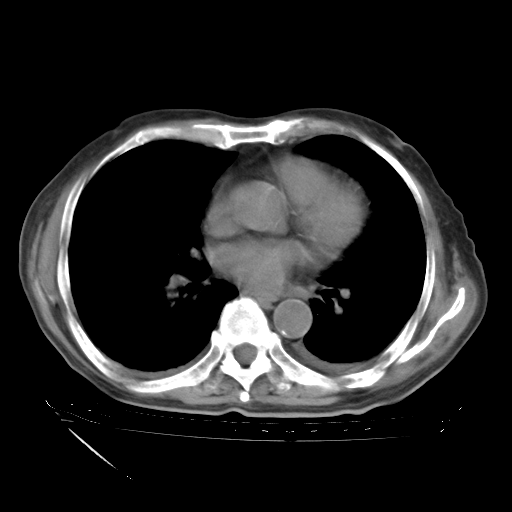

甲强龙80mg/日+抗结核治疗(异烟肼+利福霉素+乙胺丁醇)10天。复查肺部CT。

治疗10天肺部CT